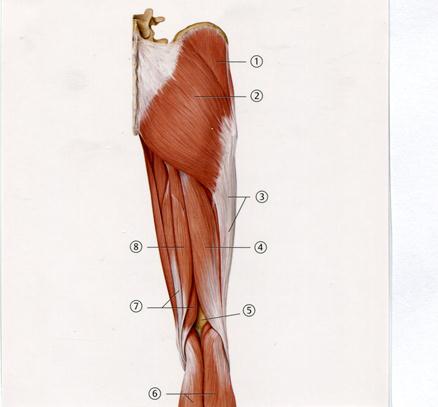

++Е Көлденең өсінді

41. Төменде көрсетілген суреттегі белгіленген № 6 бұлшықетті атаңыз.

С. Негізгі (базилярлы)